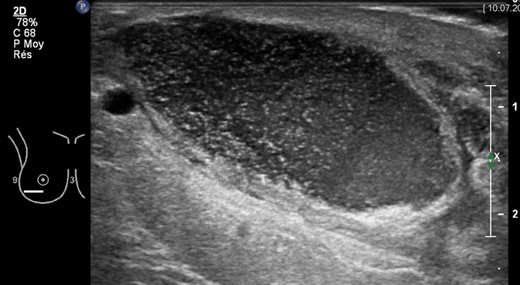

A 36-year-old Caucasian heavy smoker (1 pack/day), with no other comorbidities, presented with bilateral symptomatic breast hypertrophy. Reduction mammoplasty was performed following Thorek's technique [5]. Standard disinfection was performed with antiseptic povidone–iodine and 600 mg of intravenous (IV) clindamycin was delivered at anaesthesia induction. More than 1.1 kg of tissue was retrieved from each breast. Three weeks postoperatively, wound dehiscence associated with discharge was noted on the inferior border of the right breast. Neither redness nor heat was detected locally. The patient was apyrexial with no inflammatory syndrome (WBC count 11 g/l and C-reactive protein 6 mg/l). A smear of the discharge with liponecrosis showed low quantities of P. avidum. No antibiotic therapy was introduced at this moment and dressings with argentic sulfadiazine were prescribed every 48 h (Ialugen-plus, IBSA, Switzerland). Seven weeks postoperatively, a new red and tender induration in between the inferior quadrants of the right breast was noted. Interestingly, the patient remained apyrexial with no inflammatory syndrome. A breast ultrasound (US) showed a 4 × 4 × 15 cm encapsulated collection (Fig. 1). The abscess was drained and bacteriological examination of the purulent fluid revealed a larger quantity of P. avidum. Amoxicillin–clavulanic acid three times/day IV was started as empirical treatment for soft tissue infection. During the IV antibiotic treatment, no differences were seen in blood test parameters; however, a clinical improvement was evident with the discharge steadily decreasing. A control breast US on Day 5 post IV treatment showed remission of the abscess (Fig. 2). Results of antibiogram analysis confirmed the bacteria presence and its sensitiveness to amoxicillin–clavulanic acid. IV antibiotherapy was continued cessation of wound dehiscence (2 weeks), and then switched to oral amoxicillin for 1 month (750 mg three times a day). A breast US 1 month later showed abscess resolution and antibiotic therapy was discontinued. On physical examination, the infection had healed, and no surgical reintervention was needed (Fig. 3).

Clinical status after US-guided drainage and 2 weeks IV antibiotic therapy.